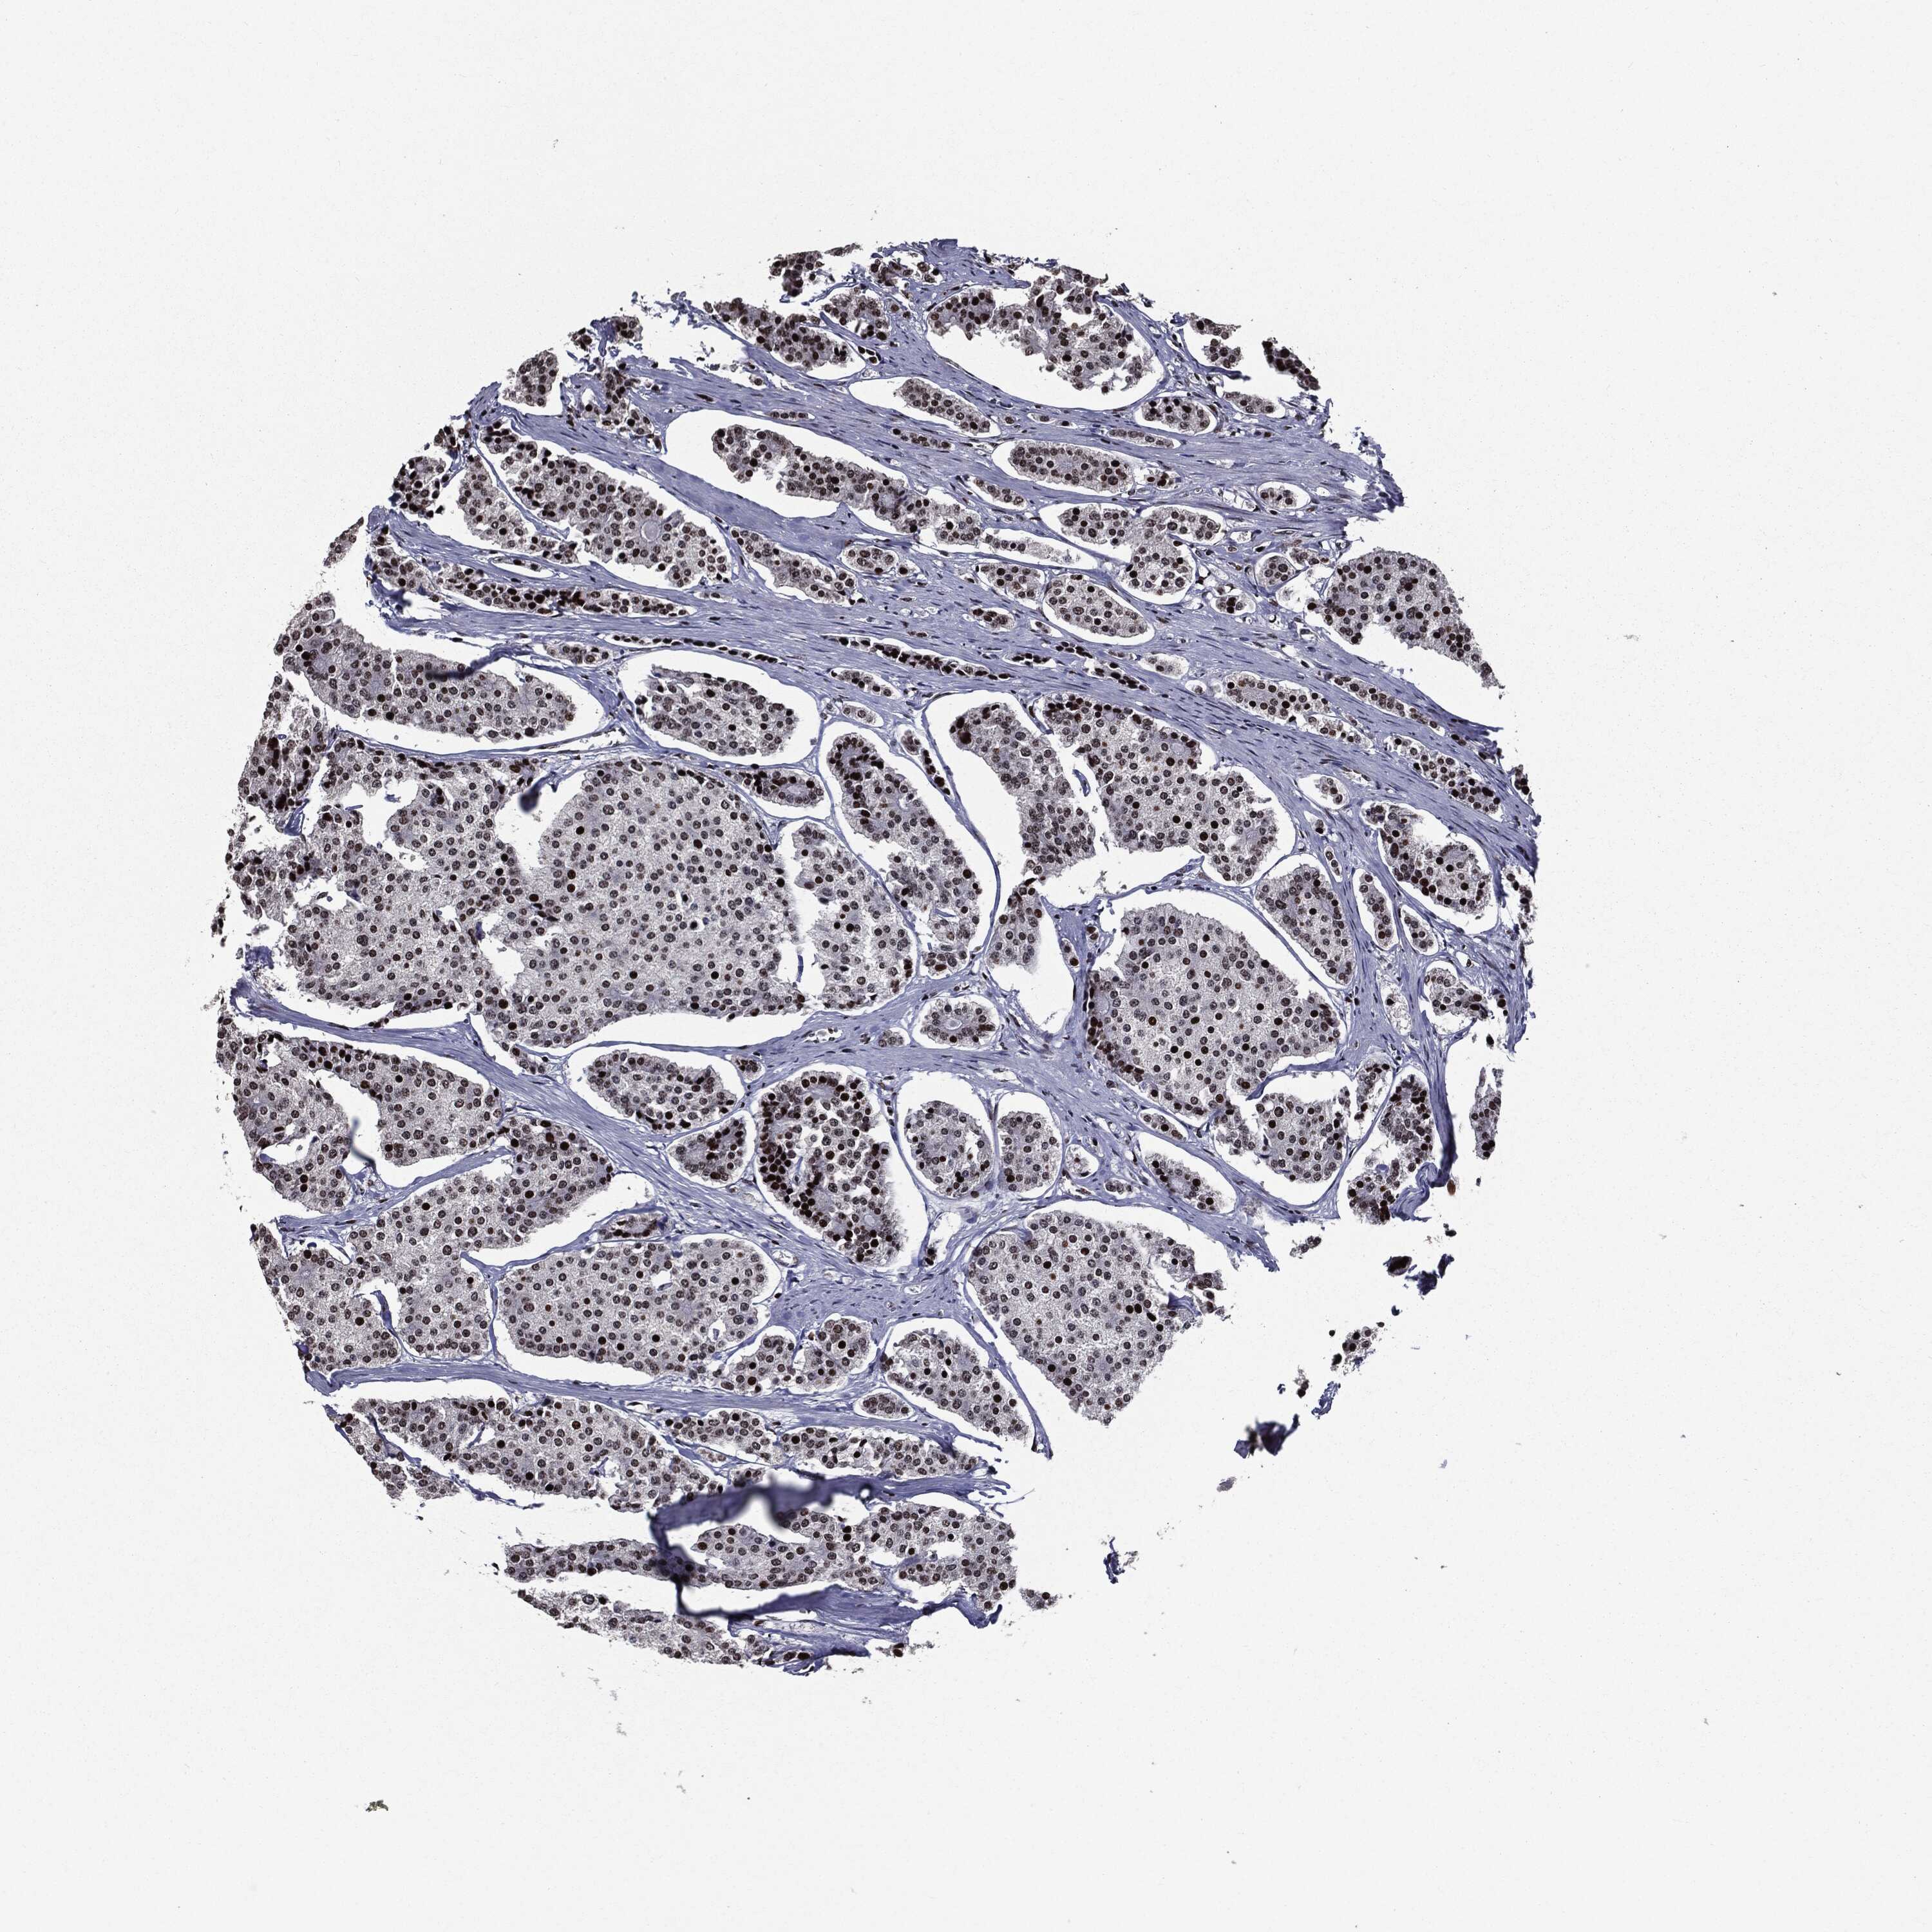

CARCINOID - Protein expressioni

A mouse-over function shows sample information and annotation data. Click on an image to view it in a full screen mode. Samples can be filtered based on level of antibody staining by selecting one or several of the following categories: high, medium, low and not detected. The assay and annotation is described here.

Antibody stainingi

Antibody staining in the annotated cell types in the current human tissue is reported as not detected, low, medium, or high, based on conventional immunohistochemistry profiling in selected tissues. This score is based on the combination of the staining intensity and fraction of stained cells.

Each image is clickable and will lead to virtual microscopy that enables deeper exploration of all samples and also displays staining intensity scores, fraction scores and subcellular localization as well as patient and tissue information for each sample.

Antibody HPA024037

Antibody HPA065325

Antibody HPA074591

Antibody CAB025417

Staining

High

Medium

Low

Not detected

Intensity

Strong

Moderate

Weak

Negative

Quantity

>75%

75%-25%

<25%

None

Location

Nuclear

Cytoplasmic/membranous

Cytoplasmic/membranous,nuclear

Carcinoid, malignant, NOS

Carcinoma, NOS